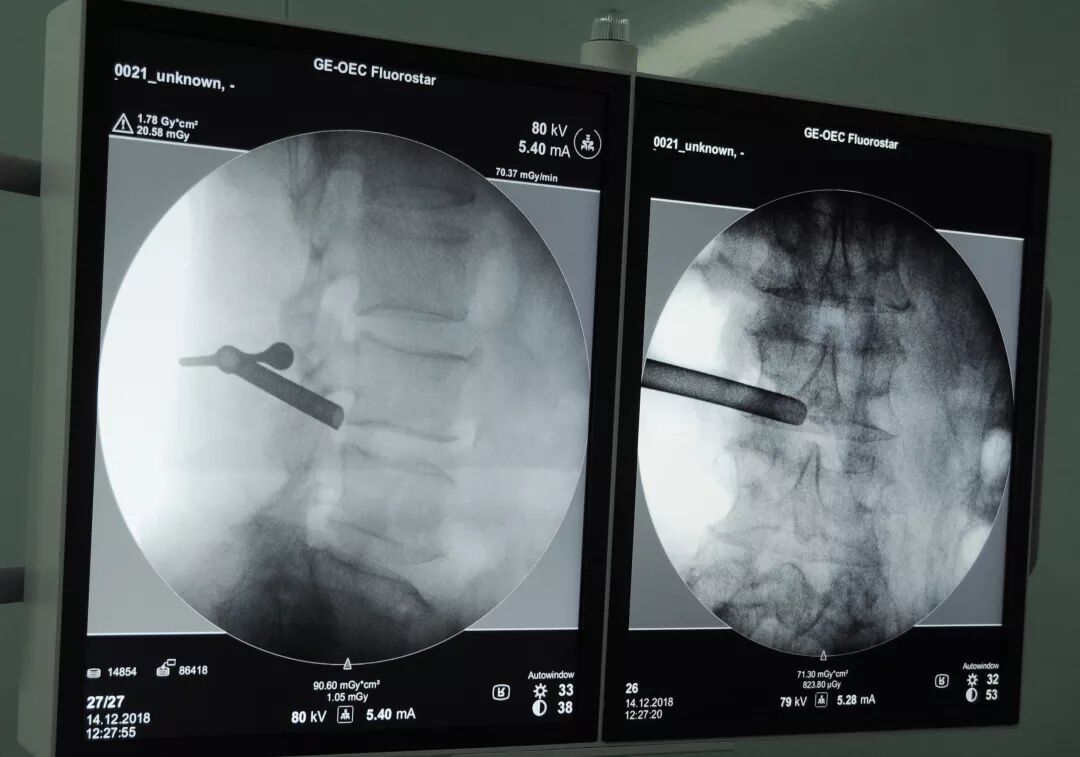

12月14日晚,乐清友义骨伤医院施行了首例椎间孔镜微创手术。接受手术的是一位82岁的老人。 医生在做术前准备 昨晚8时许,推床上的一位老人被推进了病房,医护人员正帮他挪到病床上,但想不到他却企图自己发力挪动。大家马上阻止了他,要求他乖乖听话,躺着不动,由大家将他挪到病床上。“看来我爸手术情况不错,力气还有的是,居然想自己挪到床上!”老人的女儿这样开着她爸爸的玩笑。 老人的女儿张女士是乐清卫生医疗系统的工作人员。她说,她父亲以前是乡镇干部,尽管生性乐观,但这几年饱受椎间盘突出症困扰。“我爸椎间盘突出两三年了,受病痛折磨时,站姿都歪向一边了,多方治疗一直没效果。我也是医护工作者,知道乐清友义骨伤医院拥有一流医疗设施,你们有美国进口GE1.5T超导磁共振、GE 64排螺旋CT等先进医疗设备,我就很放心将我爸送到这里住院了。因为先进的设备,它的影像非常棒,能很准确定位病灶点位,做起手术来一般都会比较顺利。” 置入环锯 张女士与兄弟姐妹们商议后,将老父亲送进了乐清友义骨伤医院。因为老人的疾病需要手术治疗,医院领导与专家高度重视,特邀浙医二院专家来院指导,由我院筋伤科主任李勇强主任医师为老人施行了椎间孔镜微创术。 “到哪儿给我爸治疗,当时我们兄弟姐妹也有不同意见。大家都知道去上海好,但考虑到老人毕竟难捱路途劳顿,于是决定就近来这里治疗。友义的医疗仪器可谓顶级装备,这个对病情诊断非常重要,又有浙医二院专家指导,这与去上海杭州没什么区别。”张女士说。 据李勇强主任介绍,老人在术后1个小时左右便顺利排尿,这种情况非常好,手术很成功。如果情况正常,几天之后老人便可下地活动。 医生在做手术 除了美国GE1.5T超导磁共振、GE64排螺旋CT,乐清友义骨伤医院还拥有GE彩超以及DR数字成像系统、椎间盘突出微创手术系统、关节镜微创手术系统、PACS影像系统等先进医疗设备和诊疗系统,擅长手法手术微创治疗。医院还邀请上海华山医院手外科和运动医学科、上海六院骨科、上海新华医院小儿骨科等知名专家教授定期来乐清坐诊和手术,全力打造“乐清人家门口的上海骨科专家医院”。